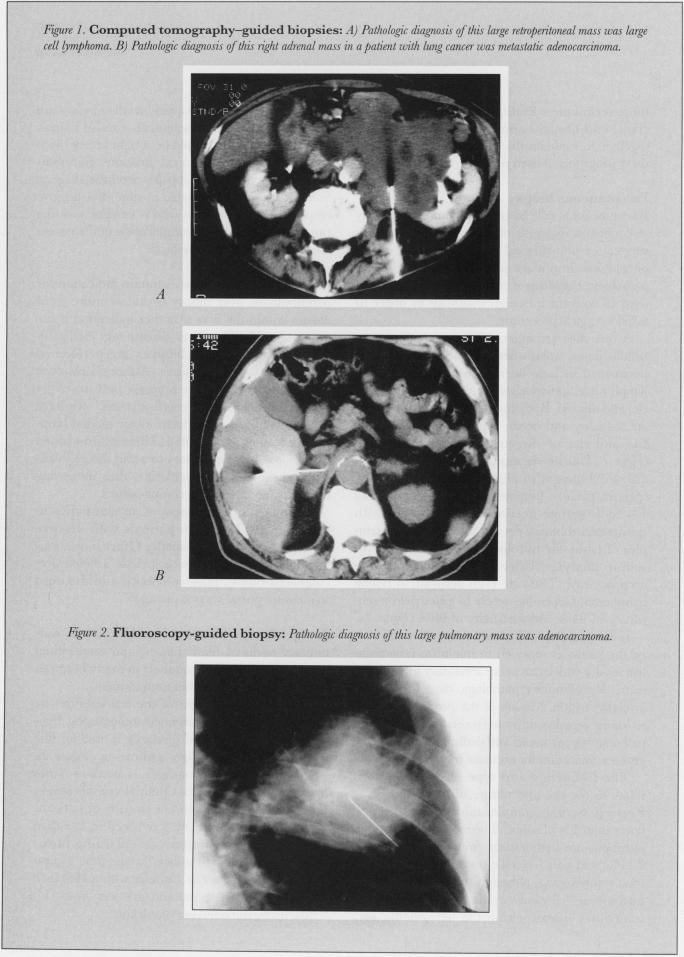

New minimally invasive interventional radiologic procedures are being developed and refined. These alternatives to standard surgical treatments have fewer complications, shorter hospital stays, and lower costs. A variety of procedures that assist in both benign and malignant diseases are particularly suited for palliative care in end-stage malignancy.